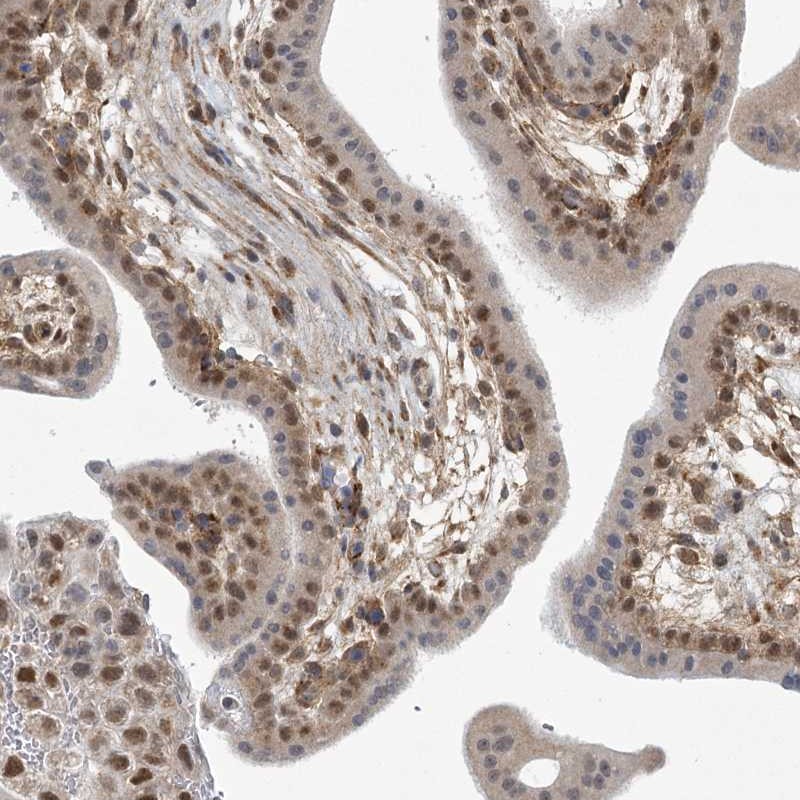

Immunohistochemical staining of human placenta shows nuclear positivity in trophoblastic cells.